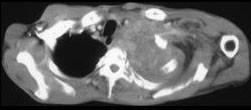

问题 男,68岁,咳嗽,胸痛,呼吸困难伴四肢无力半月余,请结合影像学检查,选出最可能的诊断 ( )

选项 A、纵隔畸胎瘤 B、恶性胸腺瘤 C、肺结核 D、淋巴瘤 E、肺癌

答案 B